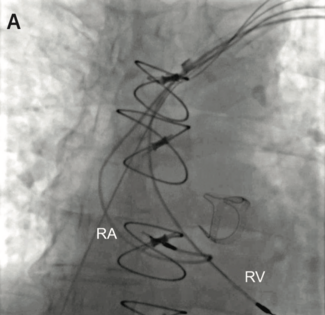

Dr. Issa presents 3 patients who underwent transvenous lead extraction for noninfectious indications utilizing an intraprocedural risk stratification approach to guide decision-making regarding lead abandonment versus extraction.

Jake Goldstein, BS, and colleagues present a systematic approach to catheter ablation in a patient presenting with ventricular tachycardia in the setting of ischemic heart disease.